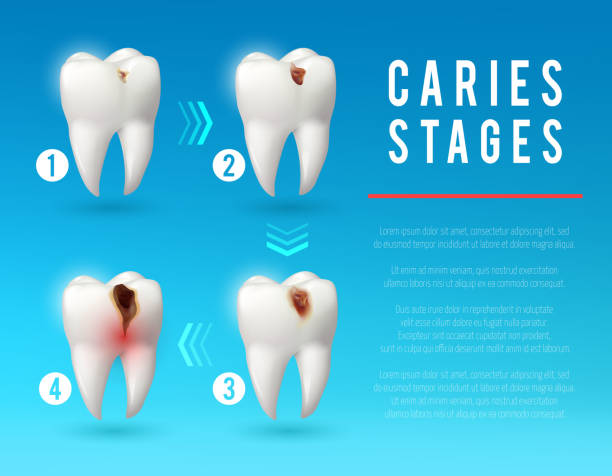

خب، اول از همه #عصب_دندان چیه؟ تصور کن یه شبکه پیچیده از رشتههای عصبی توی ریشه دندونت وجود داره. این عصبها مسئول حس کردن درد، دما و فشار هستن. وقتی دندونت دچار پوسیدگی عمیق، شکستگی یا ضربه میشه، این عصبها ممکنه آسیب ببینن و التهاب کنن. حالا چرا این موضوع مهمه؟ چون اگه عصب دندان آسیبدیده درمان نشه، میتونه باعث درد شدید، عفونت و حتی از دست دادن دندون بشه. درد عصب دندان مثل یه آلارم خطر میمونه که بهت میگه یه مشکلی وجود داره و باید بهش رسیدگی کنی.

یه نشونه دیگه، حساسیت دندونه. اگه دندونت به سرما، گرما یا شیرینیجات خیلی حساس شده، ممکنه عصب دندونت تحریک شده باشه. البته حساسیت دندون همیشه به معنی آسیب دیدگی عصب نیست، اما بهتره یه بررسی بشه. تورم و التهاب لثه اطراف دندون آسیبدیده هم میتونه نشونهای از مشکل عصب دندون باشه. در بعضی موارد، ممکنه دندون تغییر رنگ بده و تیرهتر بشه. این تغییر رنگ معمولا به خاطر خونریزی داخل عصب دندون اتفاق میافته.

چطوری میتونیم از آسیب دیدگی عصب دندون جلوگیری کنیم؟ خب، پیشگیری همیشه بهتر از درمانه! یه سری کارها هست که میتونیم انجام بدیم تا از سلامت عصب دندونمون محافظت کنیم. اول از همه، باید بهداشت دهان و دندونمون رو خیلی خوب رعایت کنیم. حداقل دو بار در روز مسواک بزنیم و از نخ دندون استفاده کنیم. مسواک زدن و نخ دندون کشیدن به از بین بردن پلاک و باکتریها کمک میکنه و از پوسیدگی دندون جلوگیری میکنه. پوسیدگی دندون یکی از اصلیترین دلایل آسیب دیدگی عصب دندونه.